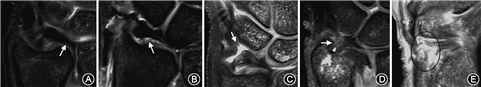

2.MRI检查:统一采用荷兰飞利浦Ingenia 3.0T和8通道专业腕关节线圈,标本背侧朝上,模拟正常腕关节检查的“超人”体位并固定于线圈中。所有标本均扫描4组序列:冠状位T1快速自旋回波序列,冠状位、矢状位和轴位的质子压脂快速自旋回波序列;视野:90 mm×90 mm;层厚:2 mm;层间距:0.2 mm。MRI由1名影像科医师和1名手外科医师共同阅读并诊断,内容包括TFC是否存在穿孔、UCL及DRUL尺侧附着部浅深层的完整性,同时于冠状位质子压脂图像中选取3个层面测量TFC中央部的最小厚度(图2A),并取均值。

中心型穿孔的MRI阳性标准为:冠状位或矢状位可见TFC低信号连续性中断,或正常TFC信号不可见(图2B);DRUL尺侧附着部损伤的阳性标准:于冠状位未见明确的低信号纤维结构附着于尺骨茎突尖部或茎突小凹处(图2C、D)。UCL损伤的阳性标准:于冠状位及矢状位可见尺月、尺三角韧带的低信号中断,或韧带结构不可见(图2E)。

1.TFC:TFC的解剖形态为一双凹面三角形,中间薄边缘厚,横断面呈哑铃型(图3A)。该形态特点是在TFC所受应力作用下形成的。由于TFC最重要的功能为缓冲尺月间的应力传导,其中心区域承受应力最大,故常厚度最小或出现穿孔。在MRI冠状位或矢状位的图像中,TFC均呈现为双凹面低信号结构。当出现穿孔时,低信号中断,穿孔区域出现高亮信号,或由于穿孔周围纤薄,图像中可见尺骨及月骨的软骨面直接接触。

2.DRUL:DRUL起自桡骨乙状切迹,分为掌侧和背侧韧带,走行于TFC的掌背侧边缘。大体解剖中,难以将韧带自软骨盘剥离,其形态为软骨盘掌背侧边缘的增厚部分。DRUL分为浅层纤维(d-c)和深层纤维(p-c)。掌背侧浅层纤维走行至TFC尺侧后汇合,止于尺骨茎突尖部。而深层纤维行至尺侧后转向近端,止于尺骨茎突凹。其作用是对TFC起锚定作用,从而维持TFC的张力并为远尺桡关节提供稳定性。自止点切断深层纤维,可见其止点为环绕尺骨茎突凹的一弧形区域,而并非局限于小凹内部(图3B)。在浅层和深层纤维之间,可见疏松的纤维结缔组织,探针可从间隙内穿过(图3C)。MRI图像中,在冠状位TFC的掌背侧边缘可见同为低信号的韧带结构,其与TFC的区别在于:二者的桡侧起点均为桡骨乙状切迹,TFC为纤维软骨结构,其起点处可见乙状切迹的软骨信号;而DRUL的起点为长入骨内的纤维(Sharpey′s fiber),此处软骨信号消失。DRUL的尺侧止点为低信号纤维结构,理想情况下浅层和深层纤维被中高信号的血管化纤维组织所分隔,但由于尺侧纤维结构细小,且混杂信号多变,现实中往往难以清晰识别。

3.UCL:UCL包括尺月韧带和尺三角韧带。二者起自TFC掌侧边缘增厚处,分别止于月骨和三角骨(图3D)。在冠状位MRI中,可于TFC掌侧层面观察到尺腕韧带;或者在矢状位上,可见自TFC掌侧边缘至月骨和三角骨的低信号韧带结构。